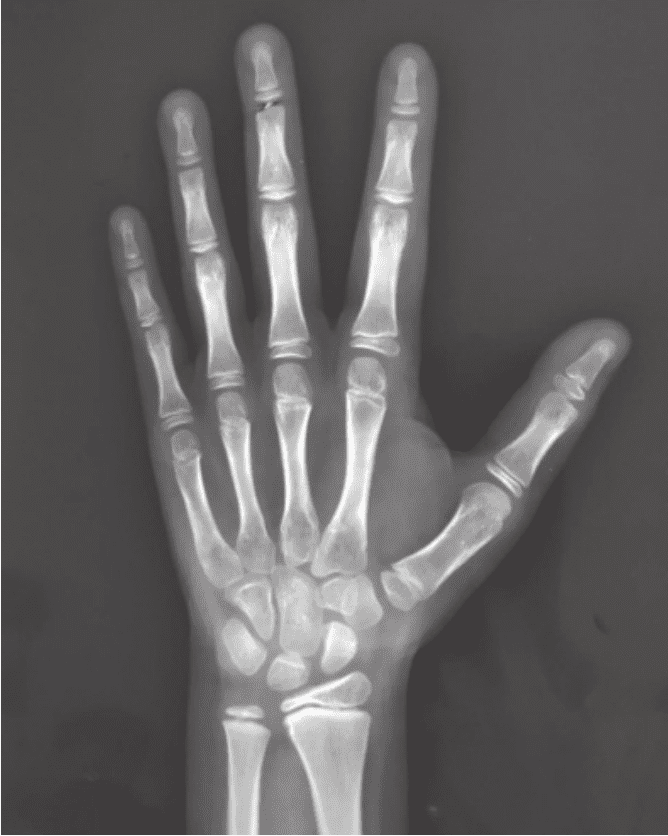

看孩子骨生理年齡一般要拍X片來(lái)進(jìn)行判斷。如果孩子是右利手,那么在拍片子的時(shí)候要拍左手;如果孩子是左撇子,那就要拍右手,這樣得到的結(jié)果會(huì)更可靠。如果年齡到了一定程度,還要拍其他的部分,比如腳后跟、肘關(guān)節(jié)、骨盆等。

拍片的作用是了解孩子真正的發(fā)育水平,預(yù)測(cè)孩子成年的身高。判斷骨生理年齡有很多方法,但是很遺憾,目前全世界還沒(méi)有一個(gè)大家都普遍認(rèn)可的精準(zhǔn)方法。

在北京協(xié)和醫(yī)院,一般比較推崇的是圖譜法。根據(jù)圖譜,我們倒推骨生理年齡的情況,再結(jié)合生長(zhǎng)發(fā)育的整體情況,測(cè)算他的骨骼到底處于生長(zhǎng)發(fā)育的什么階段。這對(duì)于我們來(lái)說(shuō)是一個(gè)非常重要的手段。當(dāng)然,這個(gè)計(jì)算過(guò)程比較煩瑣,我們一般會(huì)借助專門的計(jì)算機(jī)系統(tǒng)來(lái)進(jìn)行輔助分析。父母可能沒(méi)辦法計(jì)算清楚,但可以請(qǐng)大夫根據(jù)骨生理年齡片子幫忙計(jì)算。